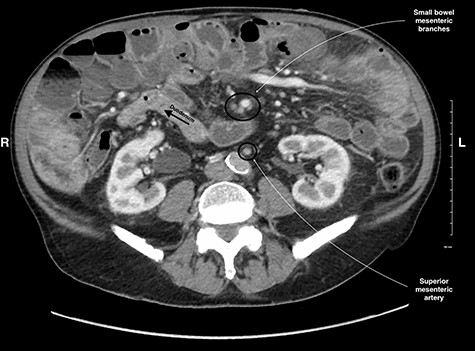

Midgut volvulus is an uncommon disease most often presenting in children, with rare occurrences in adults [3]. It is characterized by an abnormal rotation of the intestine around a fixed-point. Associated congenital conditions include gastrointestinal malrotation, jejunoileal diverticulosis and a history of abdominal wall defects [5, 6]. Acutely, volvulus can be intermittent or complete, with variable symptoms, leading to obstruction, bowel necrosis and possibly death. Chronic presentations of midgut volvulus can also occur, resulting in recurrent pain, intermittent obstruction and malabsorption over months to years. Due to its rarity in adults and variable presentation, preoperative diagnosis of intestinal volvulus is challenging. Adding to this difficulty, a classic ‘whirlpool sign’ or abnormal superior mesenteric vessel configuration is only present on CT in 30.9 and 58% of cases, respectively [3]. Retrospectively, the right-sided position of the duodenojejunal flexure and slight swirling of small bowel mesentery is visible but clouded by numerous jejunoileal diverticula (Figs 5 and 6).

CT image of the right sided position of duodenojejunal flexure, entering the intraperitoneal cavity on the right side of the abdomen.